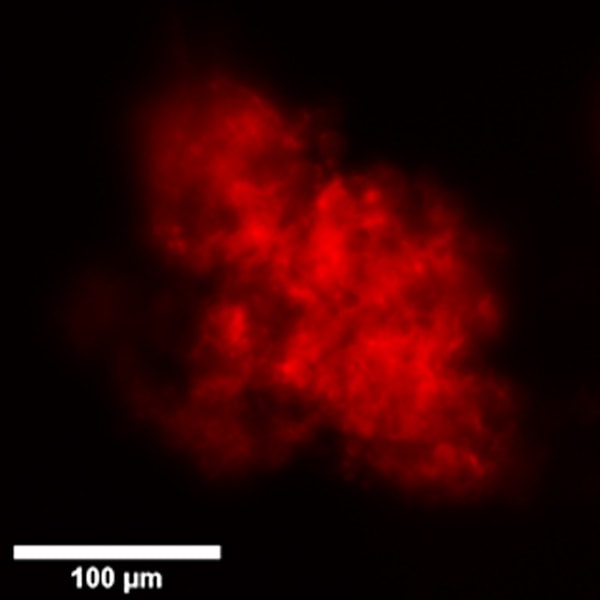

Here are shown organoids cultured in Matrigel on optical multi-well plates and generated from primary stem cells from colon cancer biopsies and stained for cytoskeleton by Phalloidin-568.

Comparison between Widefield, Confocal Spinning Disk and Super Resolution acquisitions.

X-Light V2 Confocal Spinning Disk